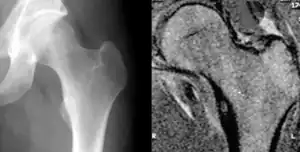

![]() | |

| Osteoid osteoma of the trochanter minor: X-ray and MRI with marked sclerosis around the nidus | |